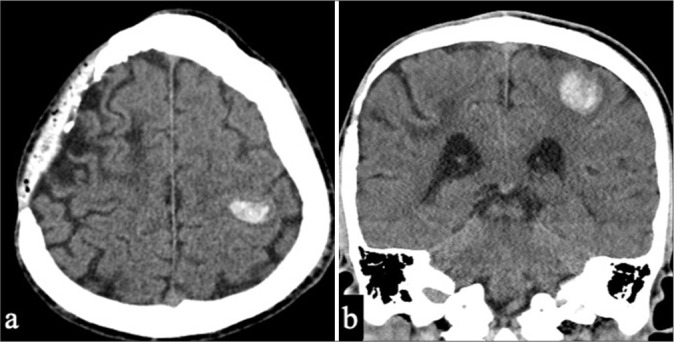

Case description: A 50-year-old man with a history of childhood right frontal hemorrhage and epilepsy presented with right upper-limb numbness. Computed tomography revealed a left parietal subcortical hemorrhage, and MRI showed bilateral occipital white matter hyperintensities, microbleeds, and right occipital leptomeningeal enhancement. Biopsy of the right occipital lesion confirmed amyloid-β deposition with mild perivascular lymphocytic infiltration, indicating probable CAA-ri. He was managed conservatively owing to the minimal mass effect and received corticosteroids as outpatients. MRI at 19 months revealed resolution of occipital hyperintensities, without neurological deficits.